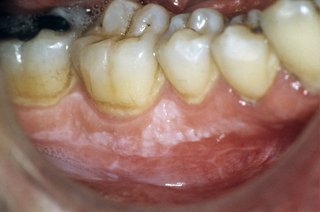

Leukoplakia to biała plama w jamie ustnej. Biała plama w jamie ustnej, która nie znika, powinna zostać sprawdzona przez dentystę lub lekarza pierwszego kontaktu.

Możliwe jest również zrobienie łatek na podłodze lub podniebieniu.

Plastry:

- nie są bolesne

- mają nieregularny kształt

- są lekko uniesione

- w obrębie plastra może być lekko czerwony

- nie można go ścierać ani zdrapać (łaty, które można usunąć, mogą być pleśniawką )